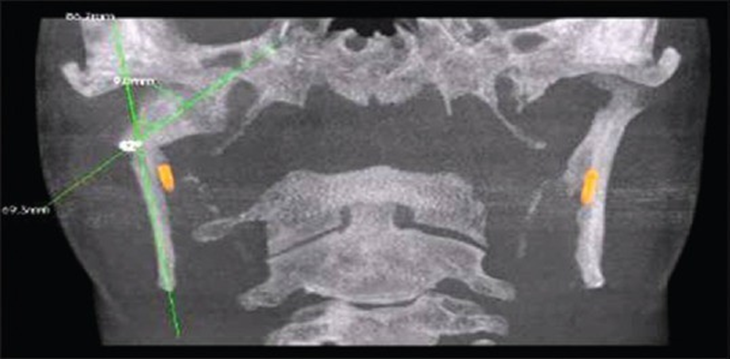

Parameters of maximal interincisal mouth opening and protrusive movements were measured from the incisal edges of the upper and lower anterior teeth while lateral movements and deviation of the mandible on mouth opening were assessed and measured with reference to the dental midline using a metallic scale. All the above parameters were assessed preoperatively and at an interval of day 3 and weeks 1, 2, 4, and 6 postoperatively for the surgical group. For the conservative group, parameters were assessed and measured preoperatively with follow-up at an interval of 2, 4, and 6 weeks postoperatively. The pain was measured using the visual analog scale (VAS) [Figure 1] based on the patient perception of pain preoperatively and at an interval of day 1, day 3, and weeks 1, 2, 4, and 6 postoperatively for both surgical and conservative groups. The height of the ascending ramus was measured on the OPG from the superior-most point of condyle to the inferior-most point of the angle of the mandible on the affected side radiographically using the ADOBE Photoshop software preoperatively and at an interval of day 3 and 6 weeks postoperatively for both surgical and conservative groups. In addition, the degree of displacement of the condyle was assessed and measured using cone-beam CT for every case to be selected for the study.

Figure 5: Measurement of degree of displacement of condyle using cone-beam computed tomography